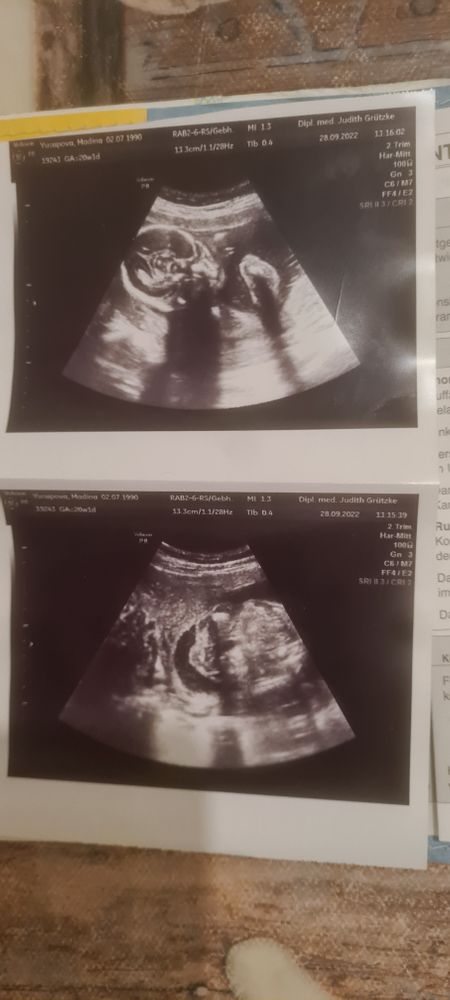

Девочки, опытные мамочки, подскажите пожалуйста, если что то разглядите)) по этим фоткам узи видно мальчик или девочка?

Ничего не видно. 😀 Вы у доктора не спрашивали? На вашем сроке он мог уже предположить пол.

Anna Fort, уже 31 неделю спрашиваю...узистке всё время что то кажется))) то похожа на девочку говорит, то не похожа...

На обоих снимках у вас головка малыша, лицо, мозг видно.... А причинное место с другой стороны находится, где пол смотрят 😅😅😅😅

31 неделя и вам врач не сказал еще😁? Если и он не видит то мы точно тут бессильны.

Muuna Alerta, врач один раз предположила девочку, даж губки показала на 24 неделе, а последующие узи она уже сомневается)